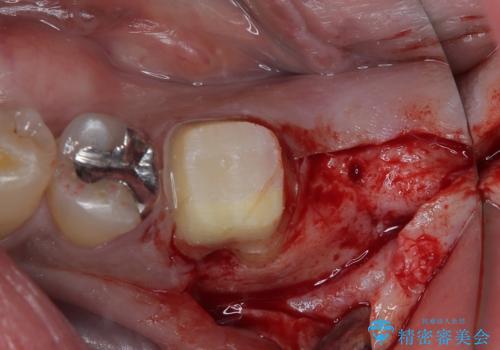

歯根が破折した歯は抜歯となるため、抜歯して病変の部分に骨が回復するのを待って、インプラントによる補綴治療を行うこととしました。

インプラント治療まで待機している間に、手前のむし歯処置されている歯が強い痛みに襲われ、確認したところ、既に神経組織が壊死している状態であったため、根管治療を行い、インプラント部と合わせて補綴治療を行いました。